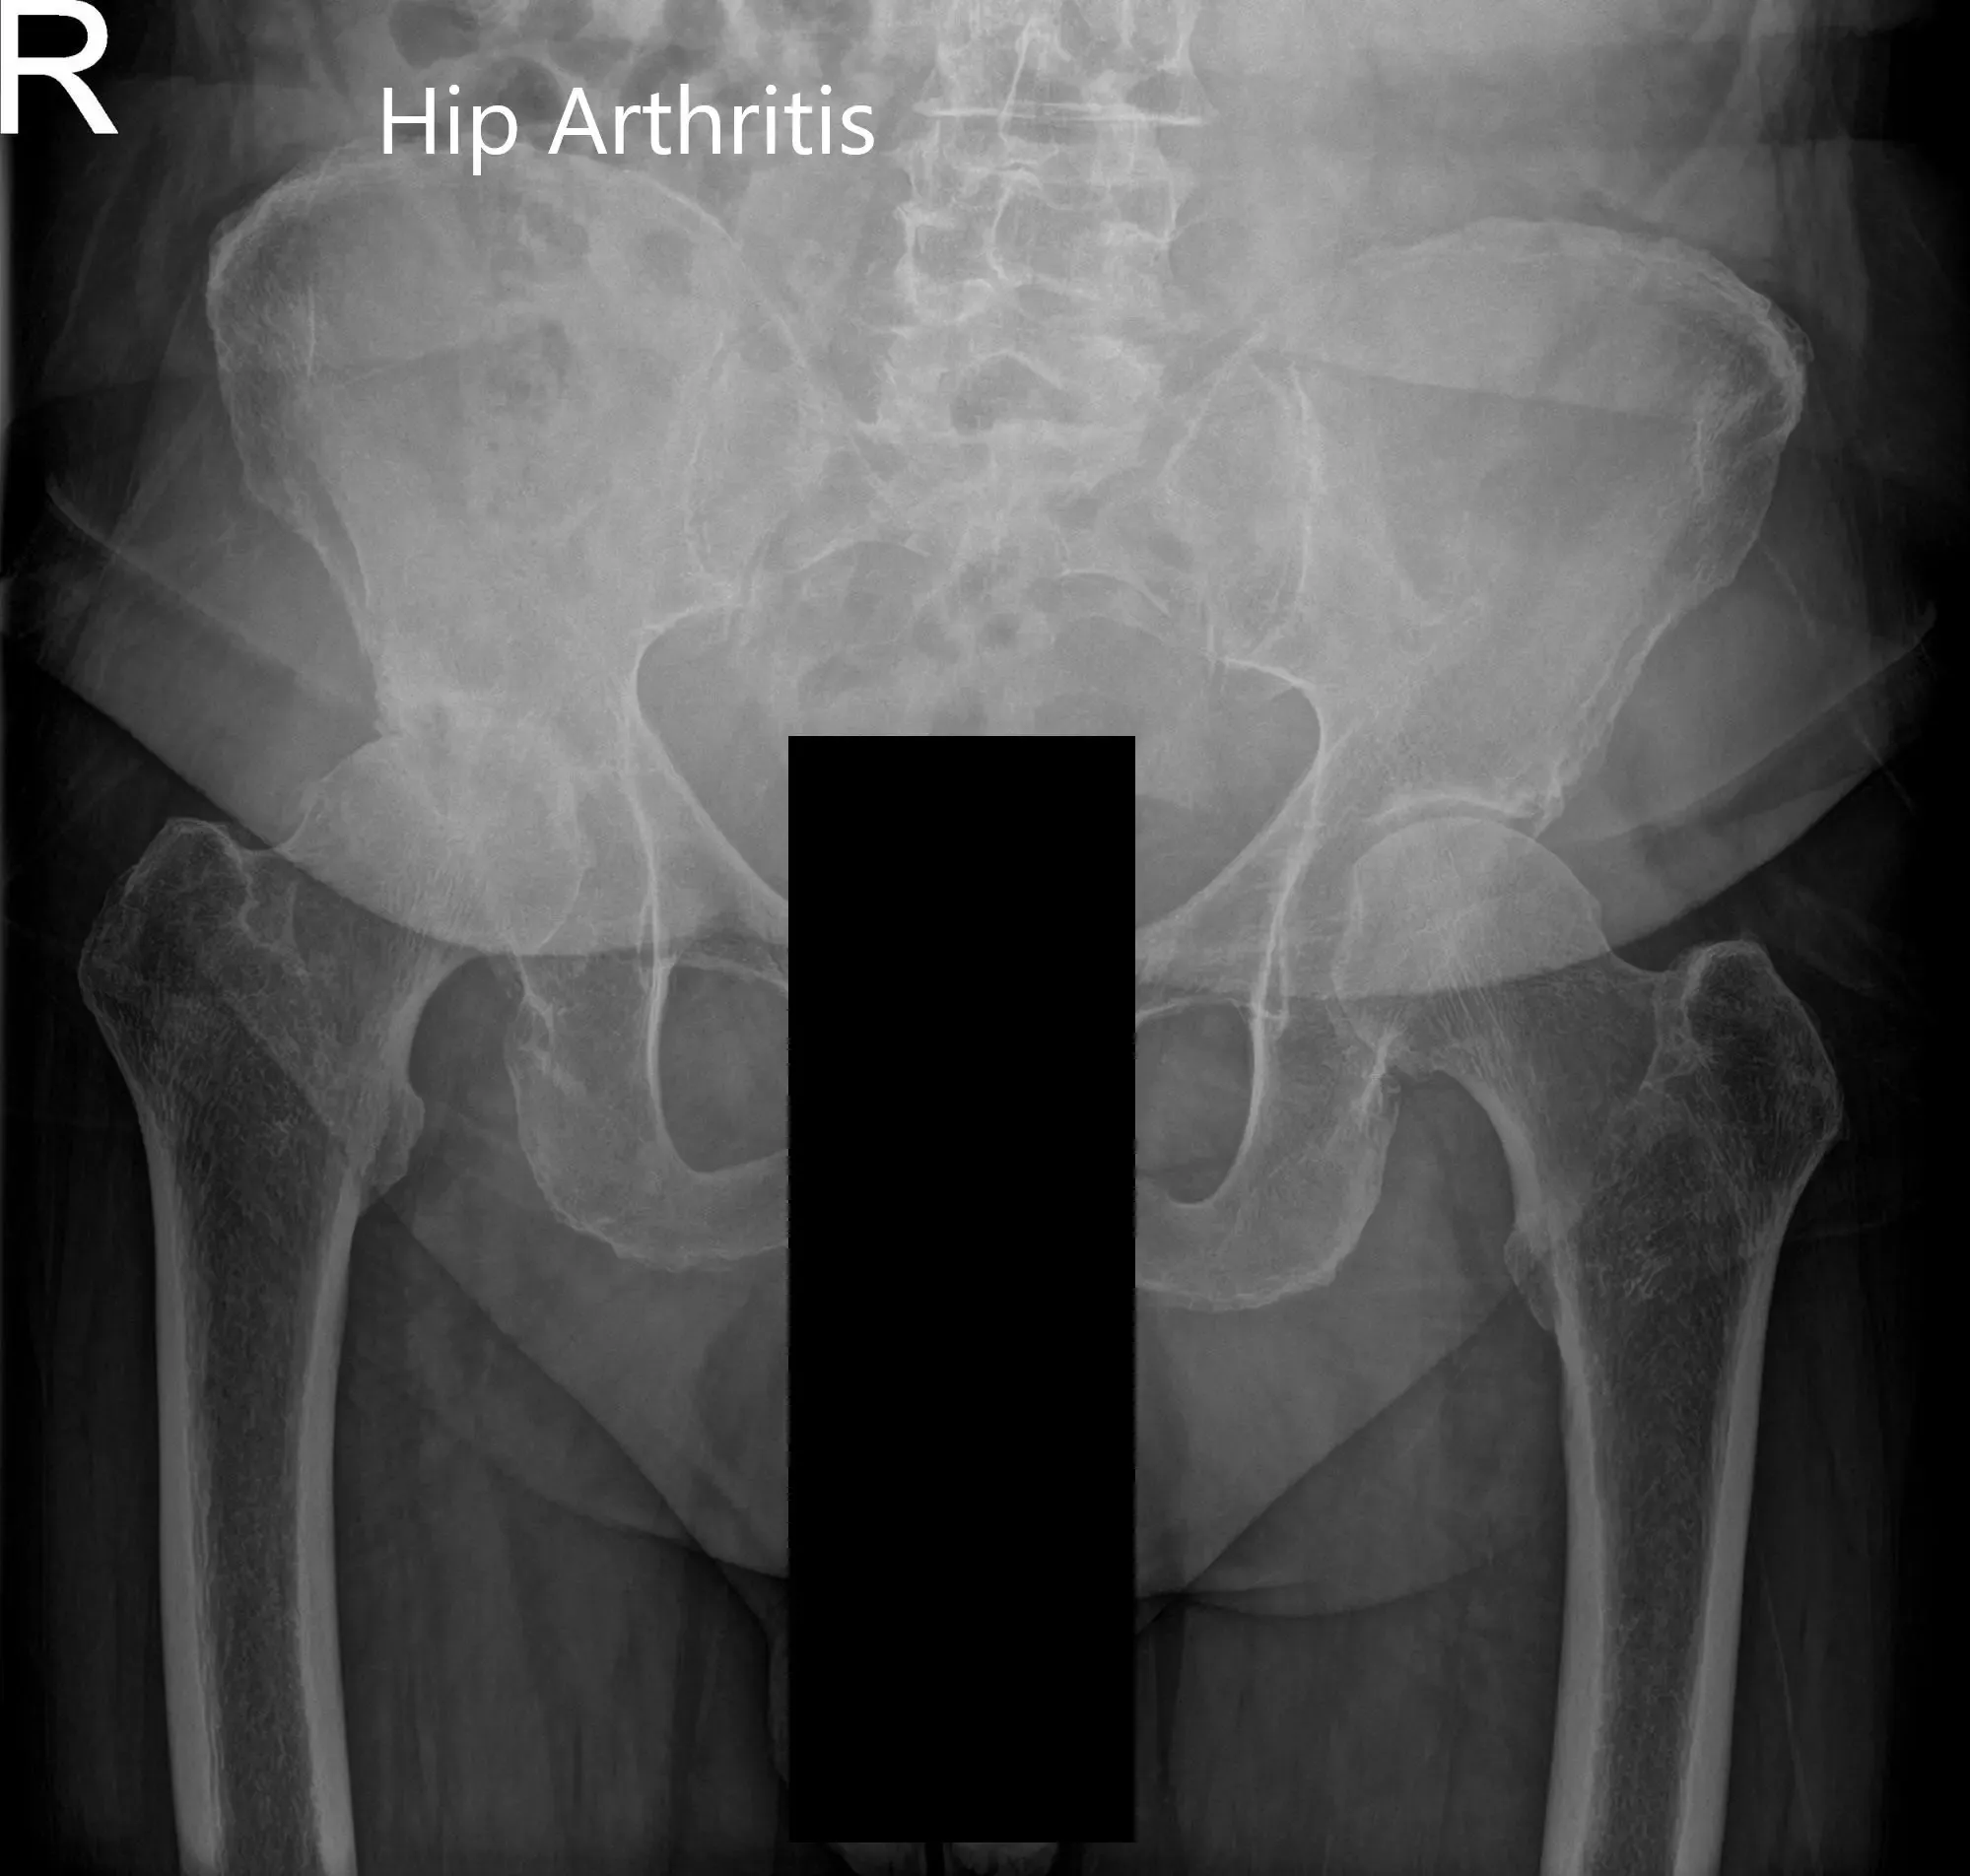

Preoperative X-ray of the pelvis, AP view, and frog-legged lateral view of the right hip.

Preoperative X-ray of Pelvis AP view and frog-legged lateral view of the right hip (image 2)